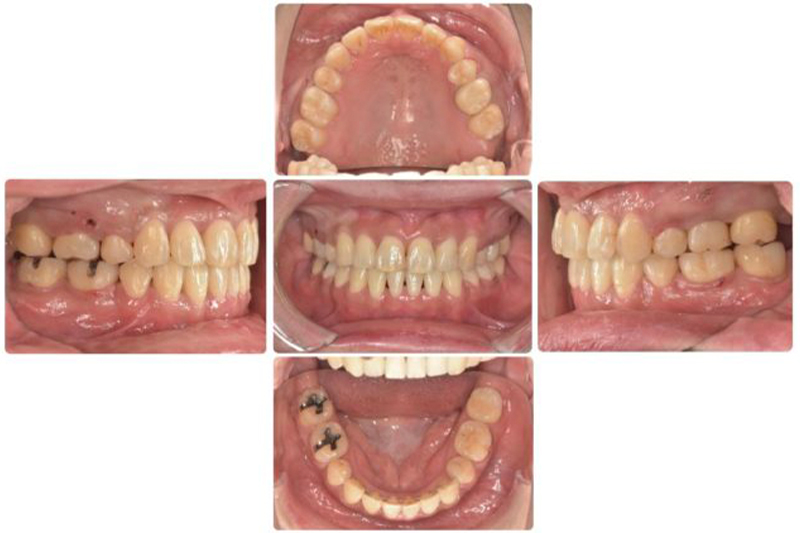

術前

術後

| 年代/性別 | 24歳/女性 |

|---|---|

| 主訴 | 歯並びを治したい |

| 治療方法 | セファロ・CT・顔貌分析後を行い、矯正(ワイヤー矯正)による治療 |

| 費用 | 70万円 |

| 備考 | ワイヤー矯正のため治療中に虫歯や歯周病に感染するリスクがある。 |

遠方にもかかわらず長らく通っていただいたので、理想的な機能的、審美的な結果を得ることができたので良かった。

本人も結婚前に治療が完了して、喜ばれていました。